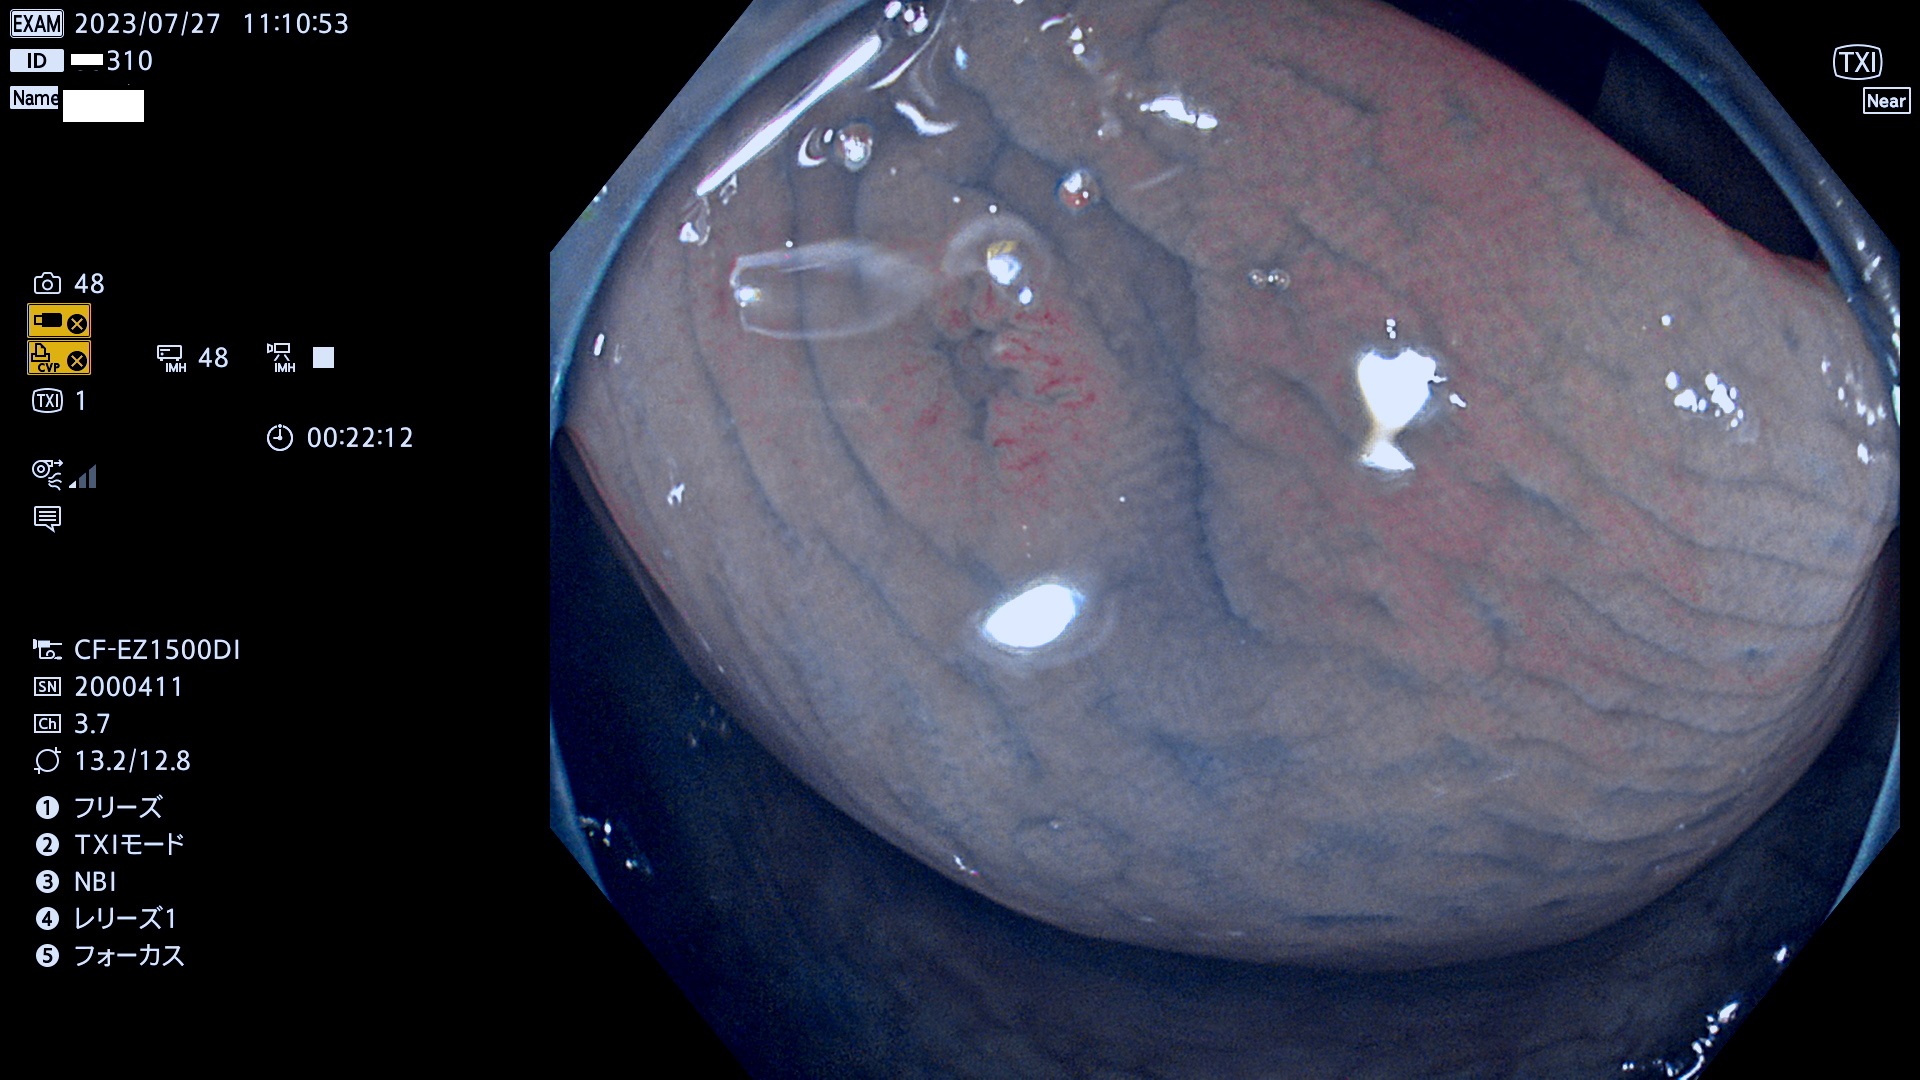

表面型腺腫(Flat Adenoma)の中で、完全に平坦な物をUb、陥凹している物をUcと呼びます。平坦隆起型(Ua)よりも、発見が難しく危険な病変です。このタイプは「内視鏡後・大腸癌の重要犯人」であり、この発見率は「腺腫発見率」よりも、重要な意味があります。

専門的)何故、陥凹していると危険? 癌遺伝子の変異が蓄積すると細胞分裂が盛んになり隆起するのでは?と通常は思われるでしょう。しかし実際は逆です。これは2022年の記事にある「細胞はストレスに直面したら細胞分裂を止める(細胞老化に入り休眠する)という生命の基本的現象」によるものです(Oncogene Stress)。細胞老化を起こすのが癌抑制遺伝子で、この安全装置(ブレーキ)が壊れると癌になります(休眠からの覚醒)。ですから陥凹は「まだ癌では無いが癌化の直前」を意味します。特に「小サイズなのに陥凹している」病変は短期間に腫瘍進化(⇒2021年記事)が起きたことを意味します(=ゲノム不安定性

専門的)Uc=De Novo癌? 内視鏡の解像度が低かった時代、このような説もありました。しかし今日の高精度内視鏡では良性の微小なUc型腺腫が日常的に見つかります。私見ですが「Ucこそが多段階発癌(Adenoma-Carcinoma Sequence)のMain Route」と考えます。

毎週の検査(木・金・土・日)に発見されたUb、Uc型・腺腫を、その週の日曜の夜にUPし1週間、提示します。

抽出の対象期間 2023年7月27日(木)〜7月30(日)の4日間(48件の検査)11件